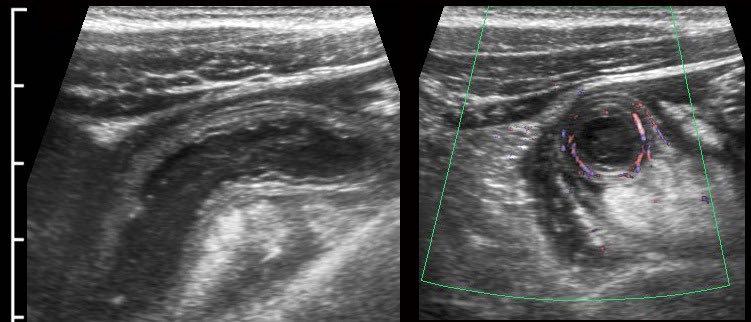

Ở bệnh nhân rất gầy này với viêm ruột thừa cấp giai đoạn sớm, siêu âm cho thấy hình ảnh giãn đoạn xa của ruột thừa.

Trên mặt phẳng A, siêu âm Doppler cho thấy tình trạng tăng sinh mạch máu mạnh ở thành ruột thừa; tuy nhiên trên mặt phẳng B, không quan sát thấy mạch máu trong thành ruột thừa do áp lực trong lòng cao.

Lưu ý hình ảnh ruột thừa giãn, tròn, không thể ép xẹp trong mặt phẳng B, phồng vào thành bụng khi ấn (đầu mũi tên), với tín hiệu mạch máu chỉ còn ở vùng mạc treo ruột thừa có mỡ xung quanh.